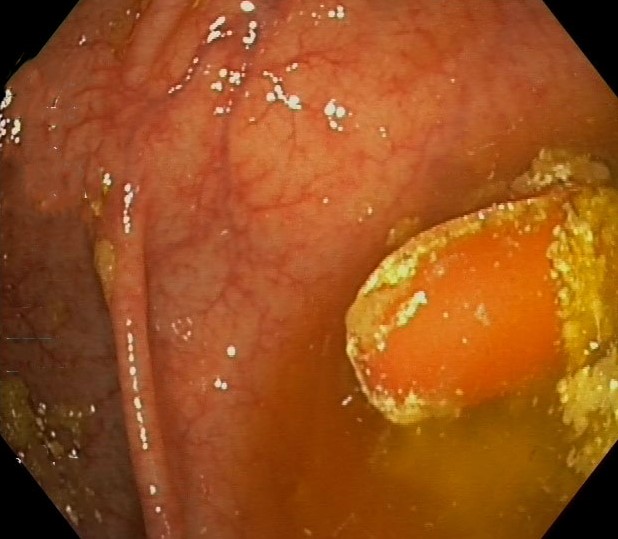

Asacol Tablets in the Caecum, Inactive Ulcerative Colitis

Asacol Tablets in the Caecum, Inactive Ulcerative Colitis. Just click on a picture!